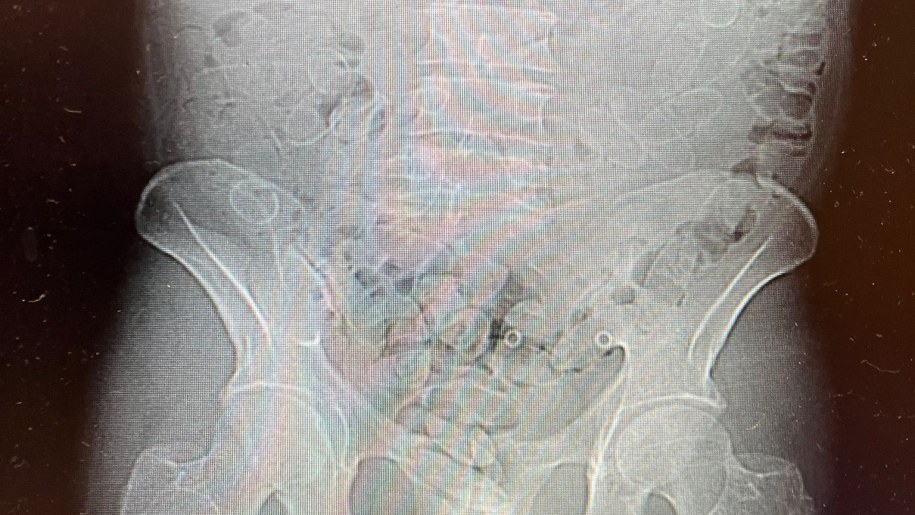

40-letni mężczyzna został natychmiast przewieziony do szpitala, gdzie badanie tomografem komputerowym potwierdziło obecność narkotyków w jego organizmie.